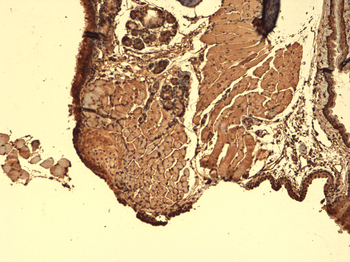

Immunohistochemical staining of paraffin embedded mouse brain tissue using anti-NIS (2.5 ug/ml)